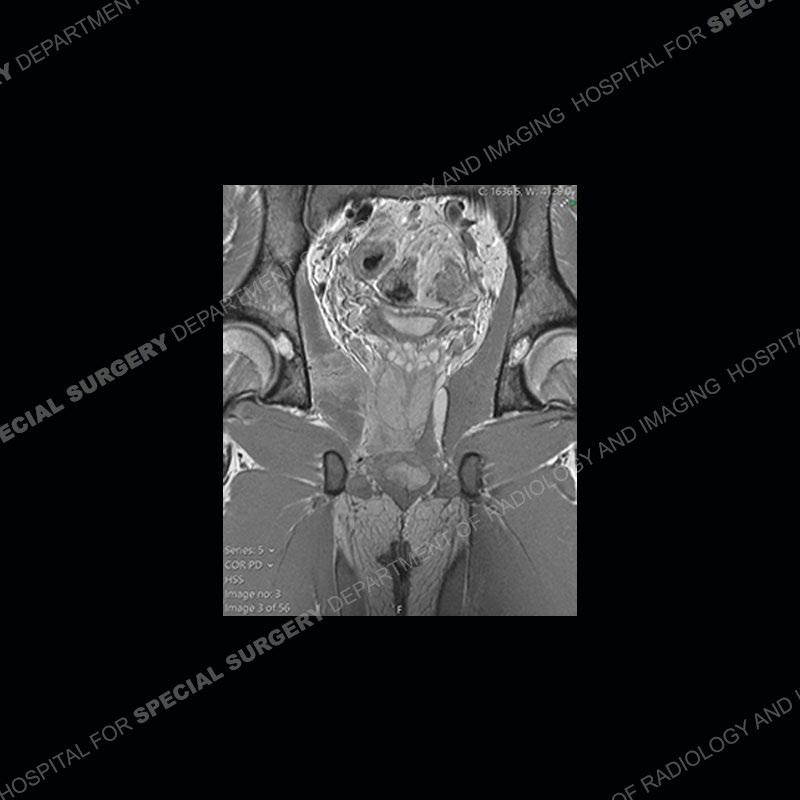

Radiographs did not demonstrate any clear abnormality. The MRI shows markedly abnormal signal of the right superior pubic ramus and abnormal signal/”mass” extending into the adjacent soft tissue. The inferior articular surface of the ramus showed what was thought to be bony destruction. CT examination shows a destructive process of the right superior pubic ramus.

Subsequent MRI in a very short time interval shows markedly increased abnormality of the ramus and increased edema and “mass” of the soft tissue. Post contrast imaging shows multiple, rim enhancing collections of the soft tissue and similar albeit less conspicuous enhancing collection of the ramus.